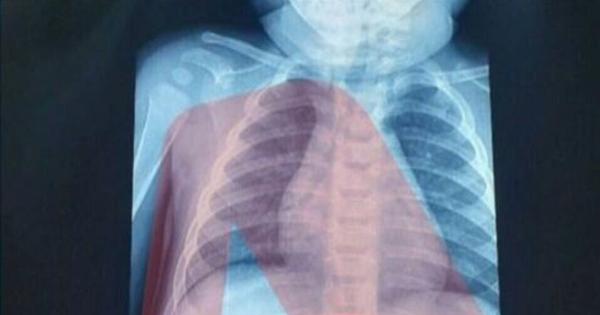

Σύμφωνα και πάλι με τις πληροφορίες της εκπομπής, στις δύο από τις τρεις περιπτώσεις καταλήγουν πως οι θάνατοι δεν οφείλονται σε προϋπάρχουσες παθήσεις ή γενετικό αίτιο, αλλά προκλήθηκαν από μη αιτιολογημένη παθολογικά, έλλειψη οξυγόνου.